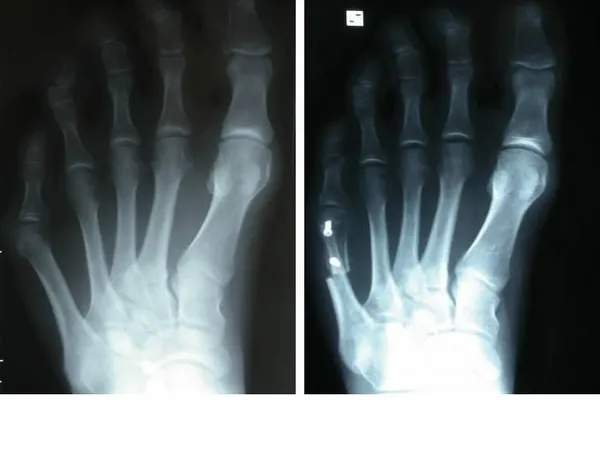

Tailor’s bunion is easily diagnosed because the protrusion is visually apparent. X-rays may be ordered to help the foot and ankle surgeon determine the cause and extent of the deformity.

Surgery is often considered when pain continues despite the above approaches. In selecting the procedure or combination of procedures for your case, the foot and ankle surgeon will take into consideration the extent of your deformity based on the x-ray findings, your age, your activity level, and other factors. The length of the recovery period will vary, depending on the procedure or procedures performed.